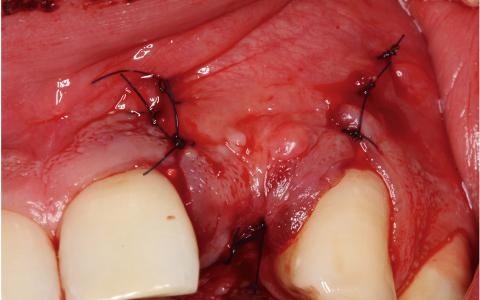

Caso Clínico nº2: Regeneración ósea

Paciente de 26 años, se le extrajo el diente hace mas de 4 años por infecciones recurrentes. Nos comenta que le salen bolitas de pus cada mes o 2 meses, el paciente fuma 10 cigarros al día y no presenta ninguna alteración sistémica.

Plan de tratamiento: Implante en zona estética con defecto óseo y regeneración ósea transversal.